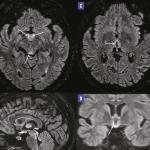

Hyperemesis gravidarum menant à une encéphalopathie de Gayet-Wernicke

Une patiente âgée de 23 ans, sans antécédents pathologiques notables, enceinte à cinq semaines d’aménorrhée, se plaint...